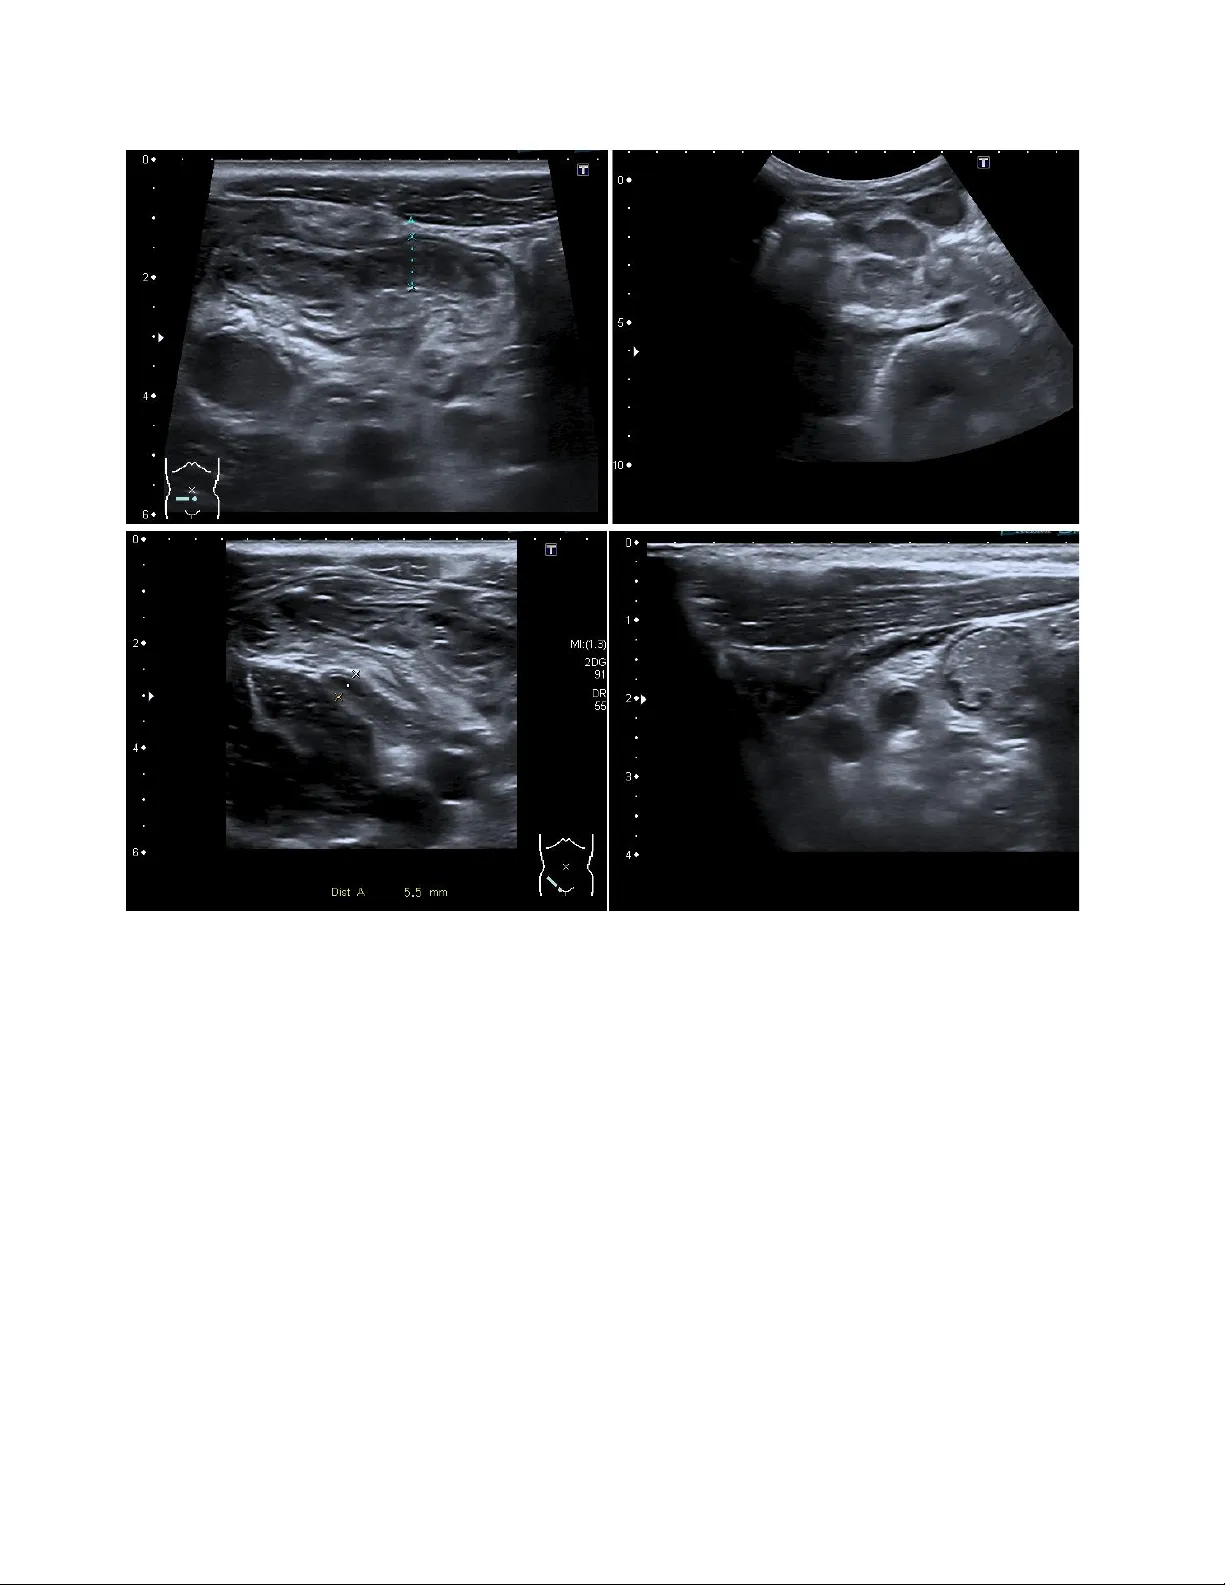

Pediatric Append icitis Detection from Ultraso und Imag es Fatemeh Hosseinabadi 1 , S e ye d ha ss a n S ha r if i 2 1 Assistant Professor of Radiology, Zahedan University of medical Sciences, Iran 2 Pediatric Cardiology Subspecialist, Day General Hospital, Iran Abs trac t Pediatric appendicitis remains one of the mo st common causes of acute abdominal pain in ch ildren, and its diag nosis continues to challenge clinicians due to overlapping symptoms and variable imaging qualit y. This study aims to develop and evaluate a deep l earning model based o n a pretrained ResNet ar chitecture for automated detection of appendicitis from B-mod e ultrasound images. We used the Regensburg Pediatric Appen dicitis Dataset, which includes ultrasou nd scans, labor atory data, and clinical scores from pediatric patients ad mitted with ab dominal pain to Children’s Hospital St. Hedwig in Regensburg, Germany (2016 – 2021). Each subject had 1 – 15 u ltrasound views covering the right lo wer quadrant, appendix, lymph nodes, and related structures. For the image -b ased classification task, ResNet was fine-tuned to distinguish appendicitis from non -append icitis cases. Images were preprocesse d by normalization, resizing, and augmentatio n to enhance generalization. The proposed R esNet model achieved an overall accuracy of 93.44%, precision of 91.5 3%, and recall of 89.8%, demon strating strong performance in identifying appendicitis across heterogen eous ultrasound views. The model effectively learned discriminative spa tial features, over coming challenges posed by low contrast, speck le noise, and anatomical v ariability in pediatric imag ing. Keywords : Pediatric Append icitis ; Ultrasound ; ResNet. 1. Intr oduc tion Acute a ppendicitis is the most common surgical emergenc y in children and adolesc ents, accounting for approximately 1 – 2 ca ses per 1,000 individuals annua lly. It typically re sults from luminal obstruction of the appendix, leading to inflammati on, bacterial ove rgrowth, and eventual perforation if left untreated. The condition can progress rapidly from uncomplicated to compl icated appendicitis, potentially resulting in peritonitis, abscess for mation, and life -threatening sepsis. In pediatric patients, early and accurate diagnosis is essenti al because younger children often present with atypical symptoms, mak ing clinical differe ntiation from other ca uses of abdominal pain more challenging. Studies have reported that diagnostic errors in appendicitis remain a sign ificant concern, with misdiagnosis rates ranging from 15% to 30% in some age groups. False-n egative diagnoses increase the risk of complications, while false-positive diagnoses may lead to unnecessary appendectomies, prolonged hospitalization, and higher m edical costs. Consequently, improving diagnostic precision is a priority in pediatric emergency medic ine [1,2]. Current diagnostic work flows for suspe cted appendicitis combine clinical evaluation, laboratory testing, and imaging. Clinical scoring systems, such as the Alvarado Score and Pedi atric Appendicitis Score (PA S), integrate symptom s (e.g., pain migration, nausea, tenderness) and laboratory markers (e.g., leukocytosis, elevated C -reactive protein) [3]. Al though these scores are helpful for risk stratification, they a re not definitive and often re quire confirmation through imaging studies. Among ima ging modalities, ultrasound (US) is the preferred first -line technique for children due to its noninvasive nature, lack of radiation, and availability in emergency settings. However, ultrasound diagnosis of appendicitis is highly operator-dependent and subject to variability in patient 2 anatomy, bowel gas interference, and body composition. Visualization of the a ppendix is successful in only 60 – 80% of cases, and diagnostic accur acy can drop significantly in obese or uncooperative children. Ev en experienced radiologists may encounter difficulty differentiating early appendicitis from mesenteric lymphadenitis or gastrointestinal infections, particularly when image qu ality is suboptimal. These limitations cre ate an urgent n eed for automa ted image interpretation systems capable of assisting clinicians with consistent and objective diagnostic insights [4,5]. In recent years, artificial i ntelligence (AI) and machine learning (ML) have revolutionized diagnostic imaging by allowing com putational models to identify complex visual and statistical patterns b eyond human perception [6-9]. I n radiology, A I has shown significant potential in tasks such as tum or detection in MRI and CT, lung pa thology scree ning in chest X-rays, and cardiac function assessment in echocardiography [10,11]. For ultrasound i maging specifically, AI algorithms have been successfully applied to fetal growth monitoring, thyroid nodule classification, and liver fibrosis staging [12-15]. The main advantage of AI-driven systems lies in their ability to learn direc tly from raw image data, thereby minimizing depende nce on subjective interpretations. Deep learning, particularly Convolutional Neural Networks (CNNs), has emerged as the corners tone of medical image analysis due to its ability to automatically extract hierarchical f eatures from low -level edges and textures to high-level structural patterns that correspond to anatomical and pathological cues. This makes CNNs particularly suitable for ultrasound data, where signal - to -noise ra tios are low, and manual feature engineering is often inadequate. Among various CNN a rchitectures, Residual N etworks (ResNets) h ave demonstrated outstanding performance in both gene ral computer vision and medical image analysis. ResNets introduce shortcut (skip) connections that bypass one or more layers, allowing the network to learn residual mappings instead of direct transformations. This study aims to harness the power of deep residual learning to improve the diagnostic accuracy of pediatric appendicitis detection using ultrasound data. We employed the Regensburg P ediatric App endicitis Dataset, a compreh ensive dataset collected from p ediatric patients admitted with abdominal pain between 2016 and 2021 at the Children’s Hospital St. Hedwig in Regensburg, Ge rmany. The dataset includes B -mode ultrasound images, laboratory findings, clinical scores, and expert a nnotations. Our primary goal wa s to train a ResNet- based CNN to classify ultrasound images as appendicitis or non -appendicitis and to assess its diagnostic performance against standard metrics. 2. Metho d 2.1 Dataset Description This study utilized the Regensburg Pediatric Appendicitis Dataset, a curated clinical dataset collected retrospectively from pedi atric patients admitted with abdominal pain to Children’s Hospital St. Hedwig, Regensburg, Germany, bet ween 2016 and 2021. Th e dataset includes a rich combination of imaging, clinical, and laboratory information to suppor t multimodal diagnostic modeling. Ea ch patient record may contain one to fifteen B-mode ultrasound (U S) images, captured from multiple abdominal regions of interest such as the right lower quadrant (RLQ), appendix, intestinal loops , lymph nodes, free fluid areas, an d reproductive organs. The ultrasound im ages ar e stored in BMP format under the US_Pictures/ directory, with filenames corresponding to subject identifiers and view indices (e.g., 23.7.bmp for patient 23, view 7) [16,17]. Figure 1Representative ultrasound images from the Regensburg Pediatric Appendicitis Da taset. Top left: Ileitis showing bowel wall thickening and inflammation. Top right: Mesenterial lymphadenitis with multiple enlarged lymph nodes in th e right lower quadr ant. Bottom left: Appendix with surro unding tissue re action, indicating periappendiceal inflammation and fat echogenicity. Bottom right: Appendix, visualized as a non-compressible tubular structure consistent with acute appendicitis [16,17] . In addition to imaging data, the accompanying file app_data.xlsx contains tabular variables summarizing laboratory test results, physical ex amination findings, and expert ult rasonographic assessments. Clinical scoring systems such as the Alvarado Score and Pediatric Appendicitis S core (PAS) were included to contextualize imaging results with established diagnostic criteria. Each subject is annotated for three outcome variables: • Diagnosis – appendicitis vs. no appendicitis, • Management – surgical vs. conservative treatment, and • Severity – complicated vs. uncomplicated (or no appendicitis). The study was approved by the Ethics Committee of the University of Regensburg (no. 18-1063- 101, 18-1063_1-101 and 18-1063_2-101) and was performed following applicable guidelines and regulations. The ethics committee confirmed that there was no need for written informed consent for the retrospective analysis and publication of anonymized routine data according to Art. 27 para. 4 of the Bavarian Hospital Law. For patients followed up after discharge, written informed c onsent was obtained from parents or legal representatives. In this work, only the Diagnosis label 4 (appendicitis vs. no appendicitis) was used for binary image c lassification. 2.2 Data Preprocessing The ultrasound images exhibited high inter-patient variability in acquisition parameters such as brightness, contrast, and spatial scale. To standardize inputs, each image was converted to grayscale, resized to 224 × 224 pixels, and normalized to zero mean and unit varia nce. Data augmentation wa s applied to improve model generalization and sim ulate clinical variability, including random rotations (±10°), horizont al flips, contrast adjustments, and Gaussian noise injection. Because multiple images were available per subject, all im ages were treated as indep endent samples while ensuring that images from the s ame patient we re confined to either the tr aining or testing split to avoid data leakage. The fina l dataset was divided into 80% for tra ining and 20% for testing, maintaining balanced class proportions. 2.3 Model Architecture We implemented a C onvolutional Neura l Network (CNN) based on ResNet a rchitecture, leveraging transfer learning to benefit from pre-le arned visual representations. S pecifically, ResNet-50 pretrained on the ImageNet datase t was fine-tun ed for the ultrasound classification task. The network structure consisted of: • An input layer receiving 224 × 224 × 3 normalized images. • The initial convolution and max-pooling layers from the base ResNet-50 model. • Four residual blo cks, e ach containing multiple c onvolutional layers with skip connections that enable residual learning and mitigate vanishing gradients. • Global average pooling to condense spa tial information. • A fully connected dense layer with ReLU activation for feature integration. • A final sigmoid output la yer producing probabilities for the binary cl asses (appendicitis vs. no appendicitis). During fine-tuning, the earlier layers were frozen to preserve general low-l evel features, while the later residual blocks and fully c onnected l ayers were retrained to ada pt to ultrasound -specific texture patterns. 2.4 Training Procedure Model im plementation and training were conducted in Python 3.10 using TensorFlow 2.14 / Keras on an NVIDIA GPU workstation. Training used the following hyperpara meters: • Optimizer: Adam (learning rate = 1 × 10⁻⁴) • Loss function: Binary cross-entropy • Batch size: 32 • Epochs: 100 (early stopping based on validation loss) • Dropout: 0.3 on the dense layer to prevent overfitting Each tr aining epoch included on-the-fly data augmentation. Model checkpoints and validation metrics were recorded at each epoch. Fine -tuning the upper residual blocks im proved convergence and boosted overall classification accuracy. 2.5 Evaluation Metrics Model performance wa s evaluated using standard classification metrics: accura cy (ACC), precision (PRE), recall (REC), F1-score, and area under the receiver-operating characteristic curve (AUC). 3. Res ults 3.1 Model Performance The proposed ResNe t-ba sed deep learning model demonstrated strong performance in detecting pediatric appendicitis from ultrasound images. After fine-tuning the pretrained ResNet-50 architecture, the model ac hieved an overall accuracy of 93.44%, a pre cision of 91.53%, and a recall (sensitivity) of 89.8% on the held-out test dataset. The F1-score, representing the balance betw een precision and recall, was calculated at 90.6%, indicating a stable and reliable detection capability. The Receiver Ope rating C haracteristic (ROC) curve exhibited an Area Under the Curve (AUC) of 0.95, reflecting excellent discriminative power be tween appendicitis and non -appendicitis cases. The confusion matrix (Figure X) illust rated that most appendicitis case s were correctly identified, with only a small numb er of fa lse negatives, pr imarily in borderline or low -quality ultrasound images. False posi tives were predominantly associated with cases showing inflamed lymph nodes or bowel wall thickening, which can mi mic appendicitis sonographically. Nevertheless, the model’ s high pre cision unde rscores its ability to minimize fa lse a larms and provide radiologists with reliable assistance in triaging ambiguous cases. 3.2 Training and Validation Curves Figure X pre sents the training and validation accuracy and loss curve s over 100 epochs. The training process exhibited steady convergence, with both training and validation accuracy improving consistently without significant overfitting. Early stopping based on validation loss prevented degradation of generalization performance. The final validation loss stabilized at 0.184, suggesting that the model effectively learned meaningful features without memorizing noise or irre levant textures from the ultr asound data. The inclusion of dropout regularization and d ata augmentation contributed to stable training behavior and robust generalization. 3.3 Visual Feature Interpretation Feature activation maps generated from the final convolutional layers using Gradient-w eighted Class Activation Mapping (Grad-CAM) provided qualitative insights into model interpretability (Figure X). The heatmaps revealed that the n etwork consistently focused on anato mically relevant regions such as the appe ndiceal area, pericecal fat, and surrounding bowe l loops, aligning well with radiologists’ regions of interest during manual assessment. This correspondence between AI attention and clinical focus reinforces the physi ological relevance o f the learned representations, suggesting that the ResNet model’s predictions are grounded in meaningful image features rather 6 than artifacts or background textures. In several co rrectly classified appendicitis cases, Grad -CAM visu alizations highlight ed inflamed tubular structures and peri-appendiceal fat echogenicity, both key sonographic indicators of appendiceal inflammation. In non-appendicitis cases, the model con centrated on other abdominal regions, confir ming the absence of the pathological pattern. Suc h visualization tools enhance model transparency and can aid radiologists in understanding the reasoning behind automated classifications. 3.4 Comparison with Previous Approaches Previous research on appendicitis detection using traditional mac hine learning methods relied primarily on hand crafted features, such as gray -level co-occurrence matrices (GLCM), edg e descriptors, and statisti cal intensity distributions, combined with c las sifiers like Support Vector Machines (SVMs) or Random Forests. Reported accuracies in these methods typi cally ranged from 75% to 85%, limited by the subjectivity of feature enginee ring and the inherent variability of ultrasound image quality. In contra st, the proposed ResNet-based deep learning approach automatically extrac ted hierarchical spatial features directly from the ultrasound data, eliminating the need fo r manual f eature design. This end- to -end learning framework not only improved accu racy to 93.44% but also offered superior robustness to noise, variable acquisition settings, and anatomical dive rsity. Furthermore, the use of transfer learning significantly re duced the amount of required labeled data and training time compared to models trained from scratch. Table X summ arizes the qua ntitative performance of the proposed model. The close alignment between accuracy, precis ion, and recall indicates that the model maintains balanced classification performance across both classes, avoiding bias toward either appendicitis or normal samples. 3.5 Clinical Relevance From a clinical standpoint, the model’s high sensitivi ty (recall) is particular ly valuable in reducing missed appendicitis cases, which can lead to severe complications if untreated. Like wise, the strong precision reduces the likelihood of false -positive d iagnoses, which may otherwise result in unnecessary imaging or surgical intervention. Integrating such AI tools into clinical workflows could assist radiologists, especially in resource-limited or high -volume settings, by providing real-time decision support and standardized interpretation across operators. Table 1 Classification performance metric Metric Value (%) Accuracy 93.44 Precision 91.53 Recall (Sensitivity) 89.80 F1 -Score 90.6 AUC 95.0 4. Dis cuss ion 4.1 Summary of Findings This study developed and validated a deep residual convolutional neural n etwork (ResNet -50) for the automatic detection of pediatric appendicitis using B -mode ultrasound images from the Regensburg P ediatric Appendicitis Dataset. The model achieved an overa ll accuracy of 93.44% , with a precision of 91.53 % and a r ecall of 89.8%, demonstrating that a d eep learning framework can accurately identify appendicitis in children using noninvasive imaging data. These findings highlight the potential of AI-assisted diagnostic tools to complement radiologist interpr etations, particularly in emergency and resource-constrained clinical environments where rapid, objective, and reproducible results are essential. The high accuracy achie ved in this study surpasses the performance r eported in many traditional machine learning approaches, which oft en rely on handcrafted features e xtracted from ultr asound intensity patterns or textural statistics. By contrast, the proposed ResNet mod el automatically learned spatially and contextually rich representations directly from imaging data, effectively capturing the structural and morphological characteristics of the inflamed appendix and surrounding tissues. 4.2 Comparison with Previous Studies Previous research efforts in automated appendicitis diagnosis have explored various im aging modalities, including CT, MRI, and ultrasound, with machine learning models such as support vector machines (SVMs), k-nearest neighbors (k- NN), and random fore sts. For example, studies using CT- based deep learning classifiers r eported accuracies between 85 % and 92%, albeit at the cost of radiation exposure — a significa nt drawback for pediatric populations. Other ultrasound-based studies e mploying traditi onal ML approaches achieved performance typically below 85% due to the limited generalizability of manually engineere d features. Our findings align with re cent advan ces in deep lea rning for pediatr ic imaging, where transfer learning using pretrained CNN architectures has shown notabl e impr ovements in diagnostic performance. The ResNet model used in this study leverages residual lea r ning, which enables the network to train dee per architectures without the risk of gradient degradation. This design allows the model to learn both low -level ultrasound textur es and high -level semantic representations critical for discriminating appendicitis from other abdominal conditions. Moreover, Grad-CAM visualization confirmed that the model’s foc us regions overlapped with clinically relevant anatomical sites, lending interpretability and biologica l credibility to the predictions. 4.3 Clinical Implications Accurate diagnosis of p ediatric appendicitis remains a p ersistent ch allenge, as clinical symptoms are often nonspecifi c and imaging results may be inconclusive. The proposed AI -driven approach has the potential to augment radiologist performance by providing a rapid, consistent, and objective assessment of ultrasound im ages. In emergency departments, such models could serve as second readers, flagging suspicious cases for further evaluation and helping to standardize diagnostic decisions across varying levels of clinical expertise. Importantly, this system operates entirely on 8 noninvasive ultrasound imaging, which is safer for pediatric patients than CT-based protocols. The integration of such deep learning systems into clinical decision support platforms could reduce the diagnostic delay and variability that curre ntly affect app endicitis management. For instance, early AI-assisted identification of appendicitis could enable faster surgical consultations, minimize unnecessary hospital admissions, and optimize th e use of imaging resources. Ultimately, these tools may contribute to lowering rates of perforation and postoperative complications by fac ilitating timely and accurate diagnosis. 4.4 Interpretability and Trust in AI Models One major barrier to clinical adoption of AI systems is the lack o f interpretability. Deep learning models are often viewed as “black boxes,” which can reduce clinician trust in automated outputs. To address this, the present study incorporated visual explainability method s such as Grad-CAM to highlight regions of interest influencing the model’s predictions. The resulting attention maps corresponded well with regions radiologists typically inspect — such as the right lower qua drant and periappendiceal fat — in dicating that the model’s reasoning process aligns with human expert interpretation. This alignment is essential for clinical validation, as interpretable AI can facilitate error analysis, improve radiologist confidence, and support educational use in medi cal training environments. 4.5 Limitations Despite promising results, this study has several limitations. First, the d ataset size, whil e relatively comprehensive, remains modest for deep learning standa rds. Larger and more diverse datasets encompassing multicenter and multi -ethnic cohorts would help improve model robustness and ext ernal generalizability. Second, only static B-mode ultrasound images were analyzed; dynamic video sequences or cin e loops might contain additional spatiotemporal cues beneficial for diagnosis. Third, although transfer learning reduced overfitting, differences in ultrasound machines, acquisition settings, and operator experience could introduce domain shifts that limit performance when appli ed to dat a f rom other institutions. Future research should explore domain adaptation techniques to address these issues. Moreover, while the model achieved high precision and recall, the clinical utili ty of false positives and false negatives must be carefully eva luated. In particular, minimizing false negatives is critical, as missed appendicitis can lead to serious complic ations. Integrating additional clinical and laboratory d ata (e .g., white blood cell count, C -re active protein, Alvara do or PAS scores) int o multimodal deep learning models may further enhance diagnostic accuracy and reduce misclassifications. 4.6 Future Directions Building upon these findings, future studies should focus on developing multimodal AI frameworks that combine ultrasound imaging with clinical metadata to emulate holistic decision-making processes. Incorporating transformer-based architectures or temporal CNNs could allow the analysis of full ultrasound video sequences rather than isolated frames, thereby capturing mot ion cues and probe dynamics. Additionally, explainable AI (XAI) tec hniques such as Layer -wise Relevance Propagation (LRP) or SHAP analysis c ould be used to provide quantitative interpretability, bridging the gap between A I pr edictions and radiological rationale. Prospe ctive clini cal trials will also be necessary to validate these systems in real-world hospital workflows and to assess how AI integration influences diagnostic speed, accurac y, and patient out comes. 5. Concl usi on In conclusion, this study demonstrates that a ResNet -based deep learning m odel can accurately and reliably detect pediatric appendicitis from ultrasound images, achieving strong diagnostic performance and clinical int erpretability. The model’s success supp orts the growing evidence th at deep learning can enhance pediatric imaging diagnostics, providing radiologists with advanced decision-support tools that are fast, consistent, and explainable. Continued research in data scalability, multimodal integration, and real-world deployment will be vital to fully re alize the transformative potential of AI in pediatric healthcare . Ref ere nces [1] Almar amhy HH. Acu te appendicitis in youn g children less than 5 y ears. Italian journal o f pediatrics. 20 17 Jan 26;43(1):15. [2] Mo stafa R, El-Atawi K. Misd iagnosis o f acute appendicitis cases in the emerg ency room. Cu reus. 20 24 Ma r 28;16(3). [3] I ftikhar MA, Dar SH, Rahman UA, Butt MJ, Sajjad M, Hayat U, Sultan N. Comp arison o f Alvarado score and pediatric ap pendicitis score for clinical diagn osis of acu te appen dicitis in child ren — a prospective study. Annals of Pediatric Surger y. 2021 Apr 15;1 7(1). [4] Po gorelic Z, Rak S, Mrklic I , Juric I. Prospec tive valid ation of Alvarado score and Pediatric Appen dicitis Score for the diagnosis of ac ute appendicitis in children . Pediatric emergen cy care. 2015 Mar 1;31(3 ):164 - 8. [5] Mittal MK, Dayan PS, Macias CG, Bach ur RG, Bennett J, Dud ley NC, Bajaj L, Sinclair K, Stev enson MD, Kharband a AB, Pediatric Emergen cy Medicin e Collaborative Research Committee of the American Academy of Pediatrics. Perform ance of ultrasound in the diag nosis of app endicitis in children in a multicen ter cohort. Academ ic Emergency Med icine. 2013 Jul;20(7):697 - 702. [6] R ahmani A, Norou zi F, Machad o BL, Ghasemi F. Psychiatric Neurosurgery with Adv anced Imaging and Deep Brain Stimulation Tech niques. International Research in Medical and Hea lth Sciences. 2024 Nov 1;7(5):63 - 74. [7] Abbasi H, Af razeh F, Ghasemi Y, Ghasemi F. A shallow review of artific ial in telligence app lications in brain disease: stroke, Alzheim er's, and aneurysm. I nternational Jo urnal of Applied Data Scien ce in Engin eering and Health . 2024 Oct 5;1(2):32 -43. [8] Z hang C, Liu D, Hu ang L, Zhao Y, Chen L, Guo Y. Classification of thyroid nodules by u sing deep learning radiomics based on ultrasound dynam ic video. Journal of Ultrasound in Medicine. 2022 Dec;41(12):2993 - 3002. [9] Norou zi F, Machado BL. Pred icting Mental Health Outcomes: A Ma chine Learning Approac h to Depression, Anxiety, and Stress. International J ournal of Applied Data Scien ce in Engineering and Health. 2024 Oct 31;1(2):98 -104. [10] Paudyal R, Shah AD, Akin O, Do RK, Konar AS, Hatzoglou V, Mahmood U, Lee N, Won g RJ, Ban erjee S, Shin J. Artificial intelligence in CT and MR imag ing for oncological applicatio ns. Cancers. 2023 Apr 30;1 5(9):2573. [11] Farina JM, Pereyra M, Mahmoud AK, Scalia IG, Abbas MT, Chao CJ, Barry T, Ayoub C, Banerjee I, Arsanjani R. Artificial intelligence-based prediction of cardiovascular dise ases from chest radiography. Journal of Imaging. 2023 Oct 26;9(11):236. [12] Son g K, Fen g J, Chen D. A sur vey on deep learning in medical ultrasound imaging. Frontier s in Physics. 2024 Jul 1;12:1398393 . [13] Akkus Z, Cai J, Boonrod A, Zein oddini A, Weston AD, Philbrick KA, Erickson BJ. A su rvey of deep -lear ning applications in ultrasound: Artificial in telligence – po wered ultra sound for improving clinical work flow. Journal of the American Colleg e of Radiolog y. 2019 Sep 1;1 6(9):1318-2 8. [14] Park HC, Joo Y, Lee OJ, Lee K, Song TK, Choi C, Choi MH, Yoon C. Au tomated c lassification o f liver fibrosis stages using ultraso und imaging. BMC medical imaging. 2024 Feb 6;24(1):36. 10 [15] Van Sloun RJ, Cohen R, Eld ar YC. Deep learning in ultrasound imaging. Pro ceedings of the IEEE. 2019 Aug 21;108(1):11 -29. [16] Marcinkevičs R, Wolfertstetter PR, Klimiene U, C hin -Ch eong K, Paschke A, Zerres J, Denzinger M, Niederberger D, Wellmann S, Ozkan E, Knorr C. Interpretab le and intervenable ultraso nography -based machine learning models for pediatric app endicitis. Medical im age analysis. 2 024 Jan 1;91:103 042. [17] Marcinkev ičs R, Reis Wolfertstetter P, Klimien e U, Chin - Cheong K, Paschke A, Zerres J, Den zinger M, Niederberg er D, Wellmann S, Ozkan E, Knorr C. Regensburg pediatr ic appendicitis dataset. (No Title). 2023 Feb 23 .